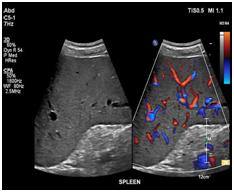

Your doctor has ordered an ultrasound of your abdomen. Ultrasound is a safe and painless procedure that uses sound waves to assess the structure of your internal body organs. The scan can help diagnose such medical conditions as abdominal masses, gallbladder disease and gallstones, as well as problems in the liver, kidneys, pancreas or spleen.

• Sound waves will bounce off certain organs and tissue in your body. This creates "echoes." The echoes are reflected back to the transducer, which converts them to electronic signals. A computer then processes the signals into pictures for radiologist evaluation.